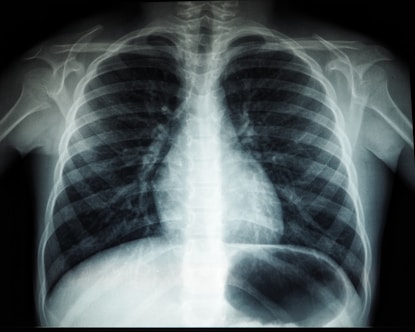

X-ray review (if available)